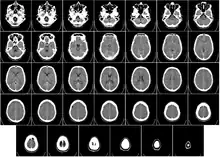

Head

CT scanning of the head is typically used to detect infarction (stroke), tumors, calcifications, haemorrhage, and bone trauma.[30] Of the above, hypodense (dark) structures can indicate edema and infarction, hyperdense (bright) structures indicate calcifications and haemorrhage and bone trauma can be seen as disjunction in bone windows. Tumors can be detected by the swelling and anatomical distortion they cause, or by surrounding edema. CT scanning of the head is also used in CT-guided stereotactic surgery and radiosurgery for treatment of intracranial tumors, arteriovenous malformations, and other surgically treatable conditions using a device known as the N-localizer.[31][32][33][34][35][36]